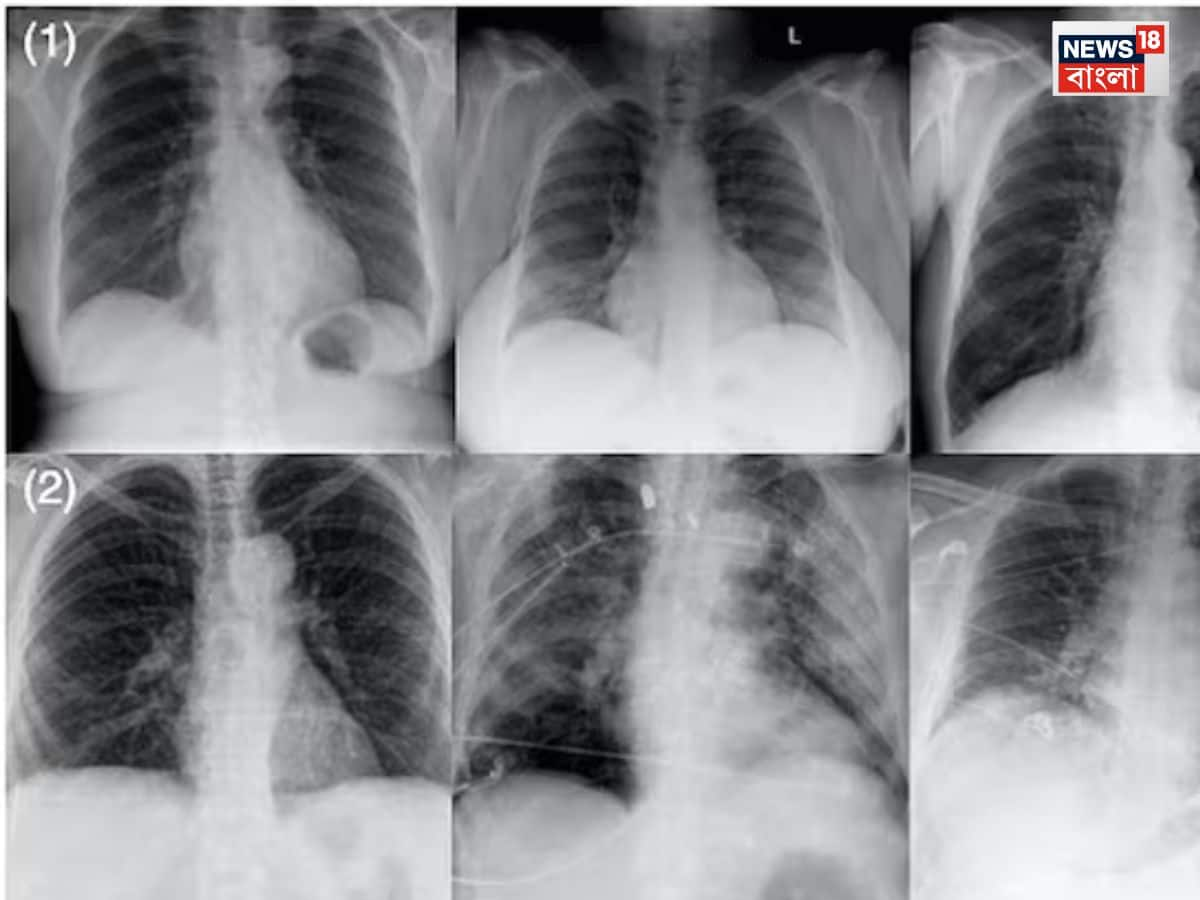

এক্স-রে:এক্স-রে হল এক ধরনের ইলেকট্রোম্যাগনেটিক রেডিয়েশন, যা মেডিক্যাল ইমেজিংয়ে ব্যবহার করা হয়। ক্যাথোড রে নিয়ে পরীক্ষা-নিরীক্ষা করতে গিয়ে ১৮৯৫ সালে উইলহেলম কনরাড রয়েন্টজেন এই এক্স-রে আবিষ্কার করেছিলেন।